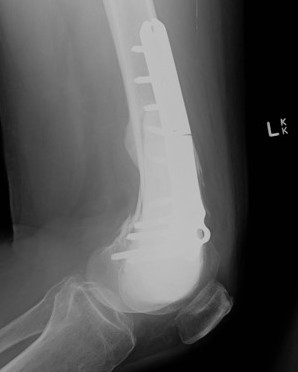

Wide resection and Allograft / Prosthesis Reconstruction

Indications

- extensive soft tissue tumour

- extensive cortical destruction

- impossible joint salvage

- multiple recurrence / failure bone cement